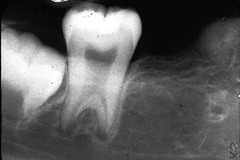

Depression on the mandible at the inferior alveolar canal- submandibular gland a)Ranula b)Pleomorphic adenoma c)epidemic parotitis (mumps) d)Stafne's bone cyst

Front

Stafne's bone cyst

Back